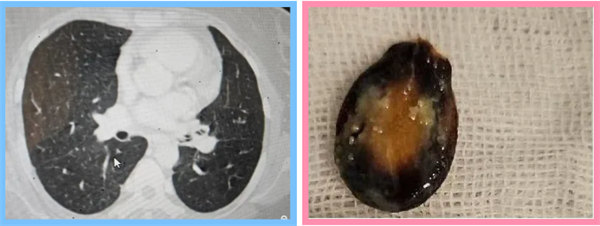

絕望之際,張先生來(lái)到了寶雞市人民醫(yī)院呼吸與危重癥醫(yī)學(xué)一科。面對(duì)張先生的復(fù)雜病情,科主任王惠霞詳細(xì)詢問(wèn)了病人情況,與主管醫(yī)生呂天樂(lè)對(duì)其進(jìn)行體格檢查以及高分辨率CT和支氣管鏡等先進(jìn)檢查手段綜合應(yīng)用,終于發(fā)現(xiàn)了隱藏在氣管內(nèi)的“真兇”——那粒導(dǎo)致張先生長(zhǎng)期咳嗽、咳痰和喘息的瓜子。

確診后,呼吸與危重癥醫(yī)學(xué)一科團(tuán)隊(duì)迅速制定了個(gè)性化的治療方案,并成功通過(guò)支氣管鏡手術(shù)將瓜子取出。隨著異物的清除,張先生的癥狀迅速緩解,咳嗽喘息癥狀逐漸消失。